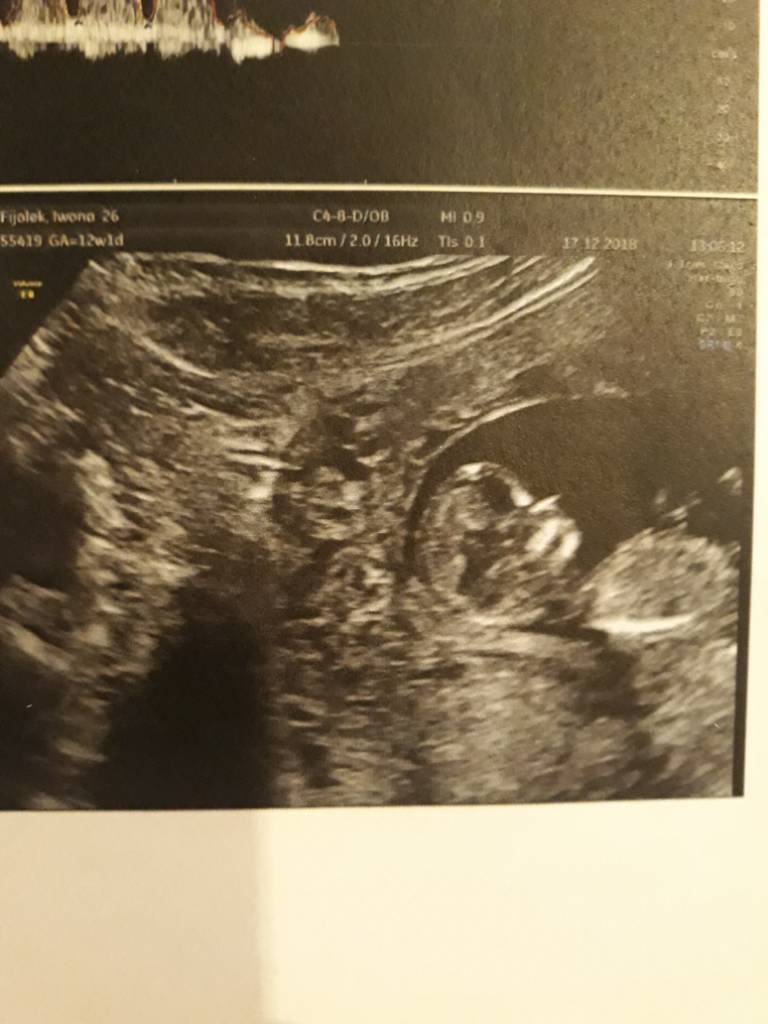

A no i dolaczam zdjecia moich Kabanoskow - jeden leniuszek ladnie pozowal a drugi wyglada jak kosmita bo sie ruszal , dzis tez do mnie machal !

A no i dolaczam zdjecia moich Kabanoskow - jeden leniuszek ladnie pozowal a drugi wyglada jak kosmita bo sie ruszal , dzis tez do mnie machal !ale z dzis zdjec nie mam bo to byl szybki.poglad ze wzgledu na upadek... aaa plecy bola ;(